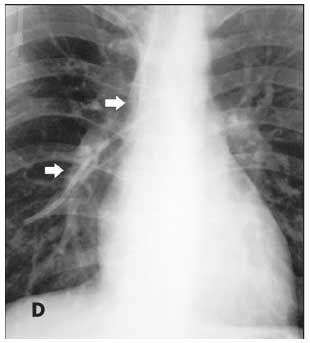

Figures B, C, and D are from a 17-year-old boy with Ewing sarcoma of the left hemipelvis. Fluoroscopy was used to confirm catheter placement, and blood return and ease of flushing the catheter were verified. During a routine clinic visit 18 months later, the patient complained of a cough and “feeling funny.” A chest radiograph was read as normal. A CT scan of the chest, obtained for routine evaluation of possible metastasis, was also interpreted as normal. However, embedded in the radiologist’s report was the comment, “A unipolar transvenous pacemaker has been placed with its tip in the right ventricular apex.” What the radiologist noticed was actually a fractured piece of CVC tubing (Figure B, arrow). Careful inspection of the patient’s earlier “normal” chest radiograph showed the fractured piece of tubing within the right atrium and ventricle (Figure C, arrow). A second chest radiograph showed the tubing fragment lodged in the right pulmonary artery extending into the right lung (Figure D, arrows). No POS was seen in a review of the patient’s radiographic records.

Common sites for embolization of the distal fragment are the central veins, right atrium, right ventricle, and pulmonary arteries. Surprisingly, most patients are asymptomatic. The most common symptom is pain or pressure during an attempt to use the damaged catheter.8 Other common symptoms are cough, palpitations, and swelling around the port site caused by fluid extravasation. Sustained ventricular tachycardia, although rare, may also occur.5 Retrieval of the distal fragment is commonly via a percutaneous vascular route; in some cases, open thoracotomy or even electing to leave the fragment in place may be preferable.9

The second case highlights the necessity of careful inspection of all radiographic images ordered and their respective reports. The “funny feeling” the patient had been experiencing may have been related to cardiac arrhythmias caused by stimulation of the right ventricle by the detached tubing fragment.